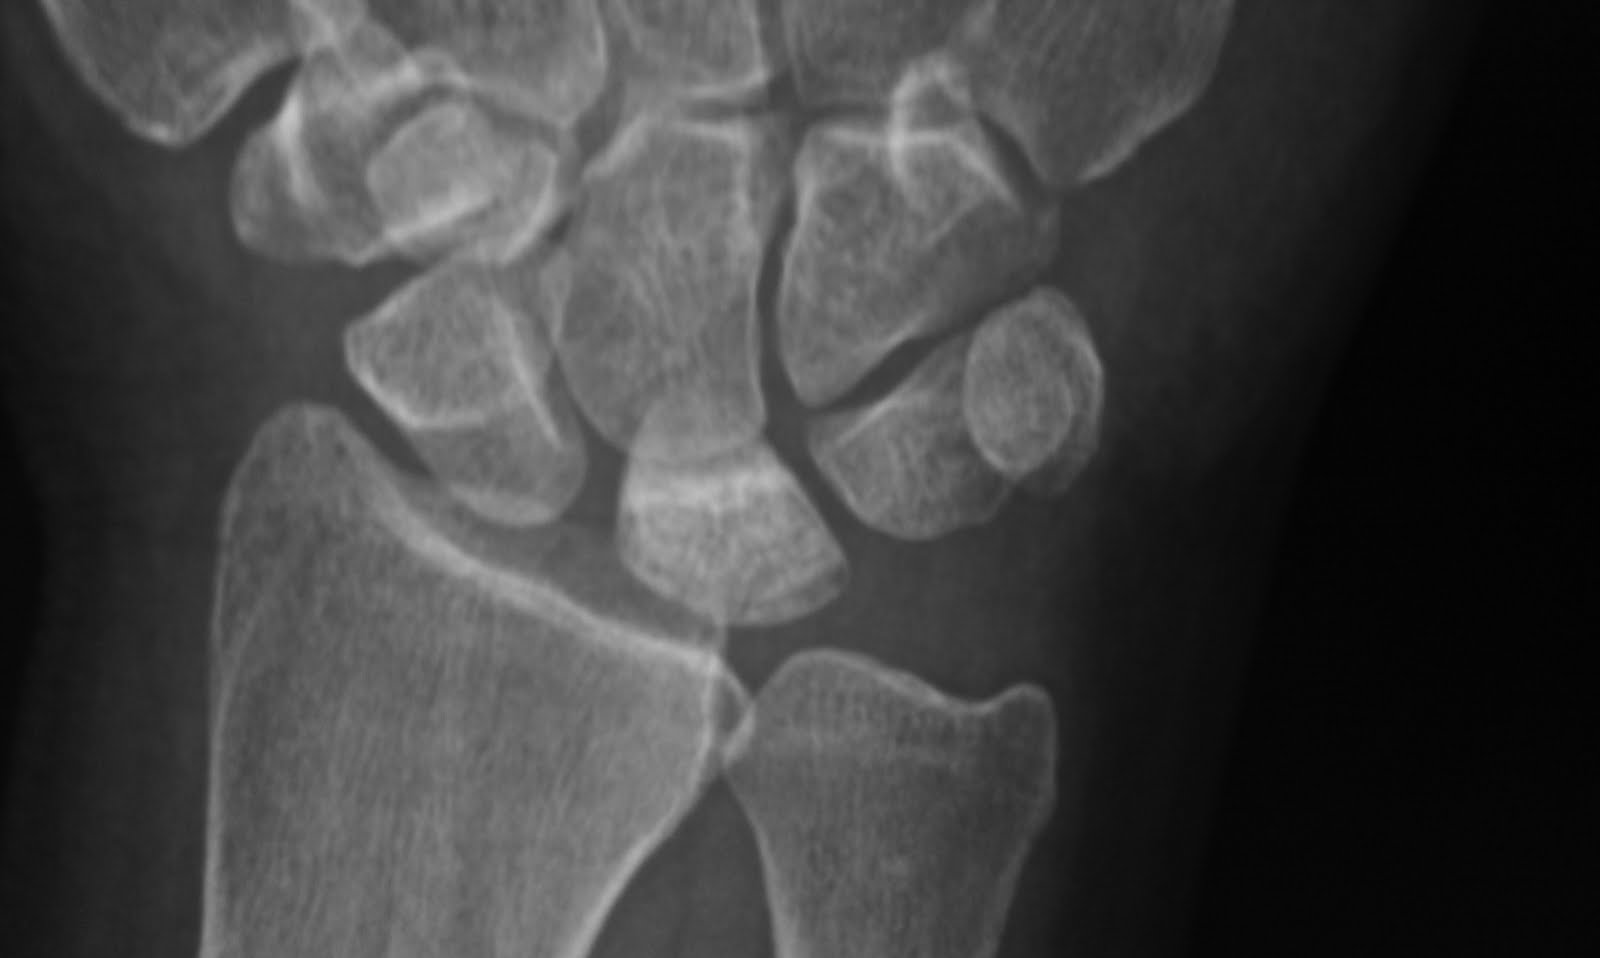

Keinbock's disease

Avascular necrosis of lunate